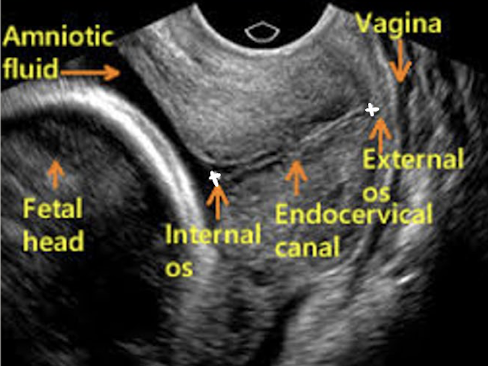

cervix: transabdominal technique

scan through amniotic fluid/bladder to image cervix

measure length of cervix from internal os to external os

do not include vaginal canal in measurement

cervix: transvaginal technique

GOLD STANDARD method

bladder is empty

define cervical canal—take close-up shot (75% of screen)

measure length from internal os to external os